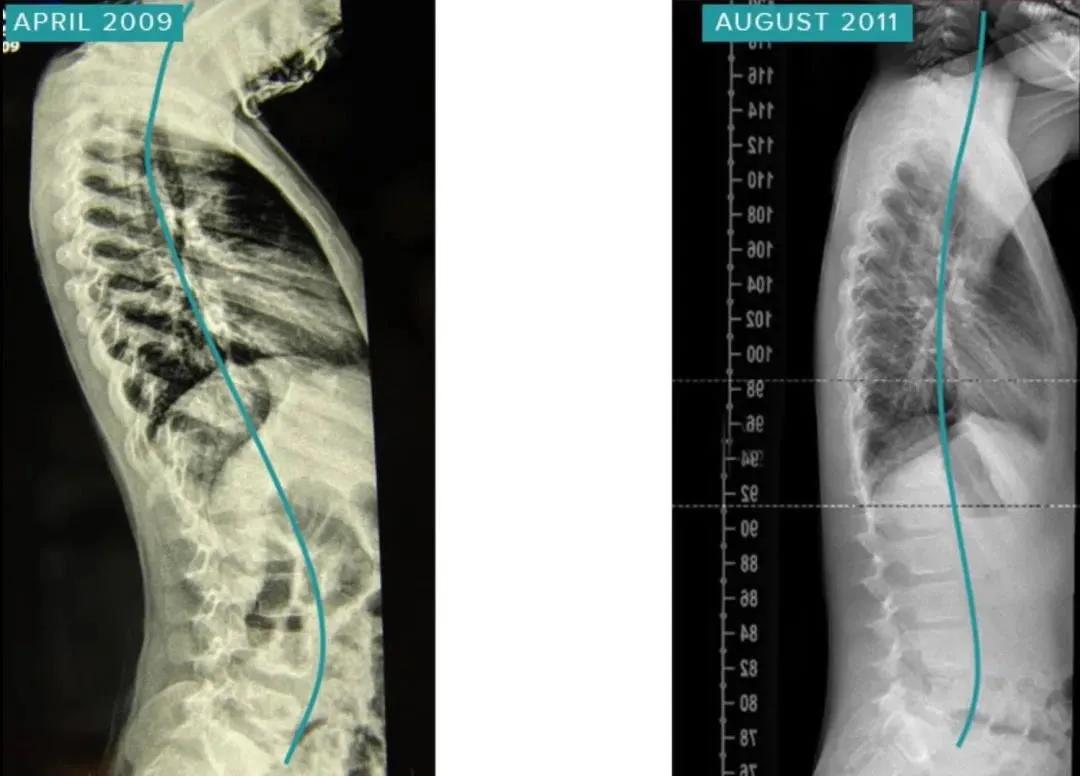

该患者在治疗有深部前凸和后凸。经过2年的螺旋稳定化治疗,患者的脊柱曲线恢复正常,长高了15cm,同时身型更加挺拔,体态更加健康。

胸椎30°Cobb-> 8°Cobb(提高22°)

腰椎21°Cobb-> 1°Cobb(提高20°)